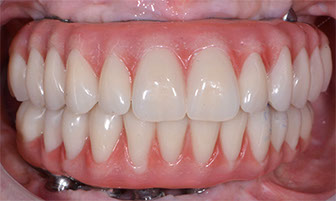

3.2 Immediate Load Prosthetics (All-on-4)

This part of the course covers the methods of diagnosis, practical treatment planning, pre-surgical prosthodontics, imaging, armamentarium, and clinical techniques needed for this exciting treatment modality. Crucial to this treatment modality is the understanding of the biomechanical aspects and functional loading of the immediate full arch prostheses. The aesthetic and phonetic requirements, space requirements, laboratory communication, insertion techniques post-operative follow-up and hygiene requirements are key to this treatment.

Aesthetic and phonetic requirements

Space requirements

Establish a systematic and organised approach to the prosthetic techniques for this modality of treatment